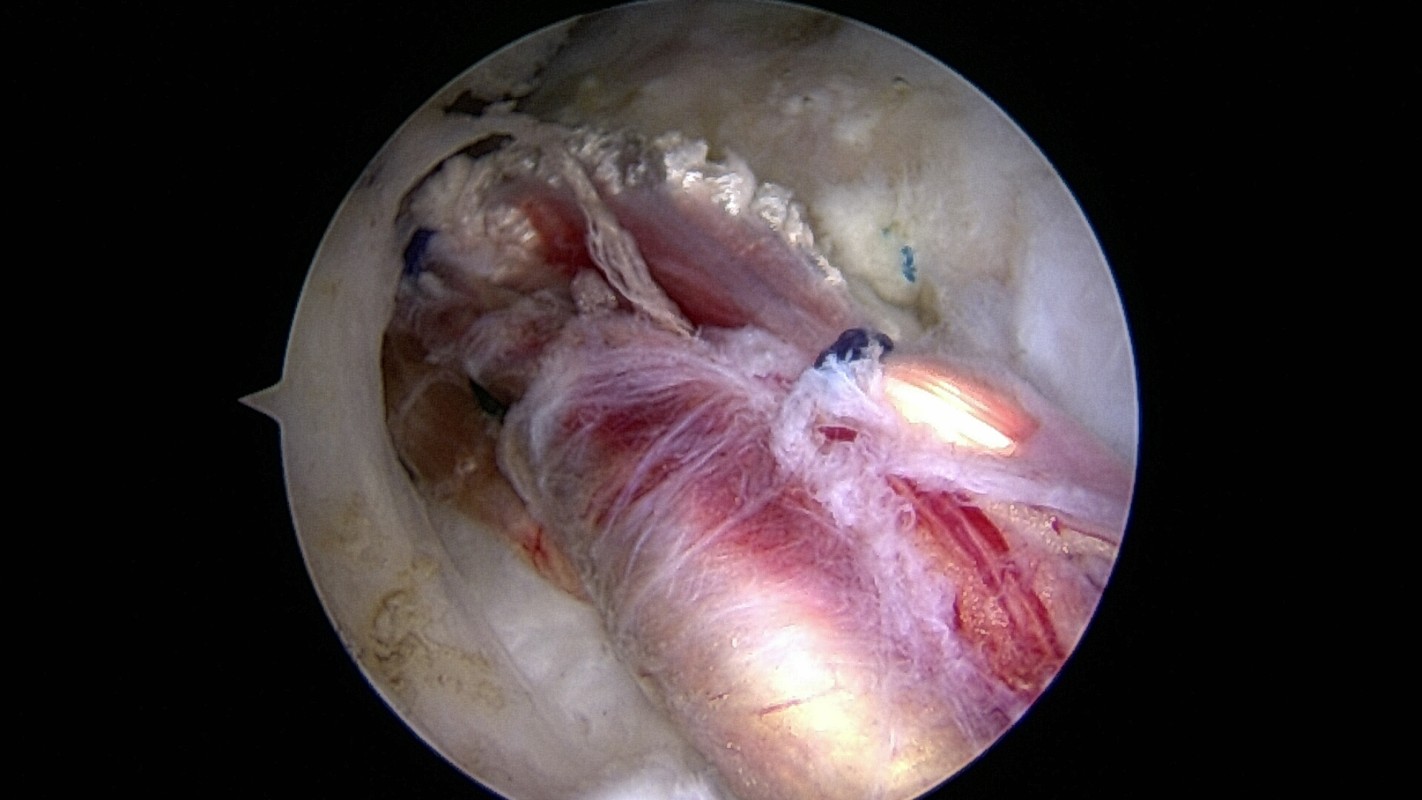

Technique de réparation de(s) tendon(s). (SS, IS, SSC )

La faisabilité de cette réparation est évaluée par IRM ou athro-scanner, mais des imprévus quand à la qualité tendineuse rencontrée durant l’intervention sont possibles : l’intervention planifiée peut donc différer de celle effectivement réalisée ! De petites vis (en titane ou résorbables) munies de fils sont introduite dans l’os de l’humérus. Des passe-fils miniaturisés permettent de fixer le tendon à l’os.

Réparation de tendon: perforation

Réparation de tendon: récupération des fils

Utilisation du passe-fil